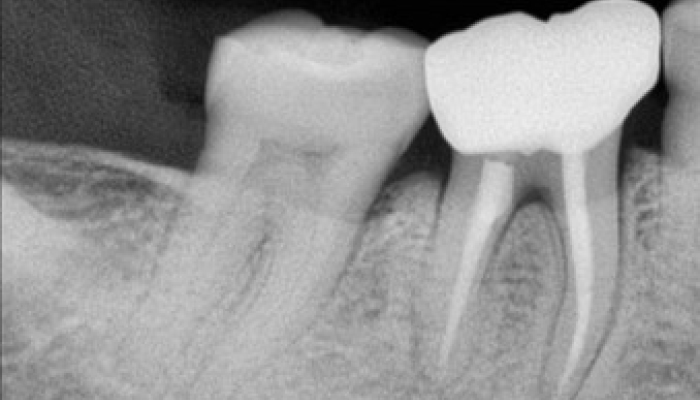

신경치료 전후 사례

• 치료 전

치료 후